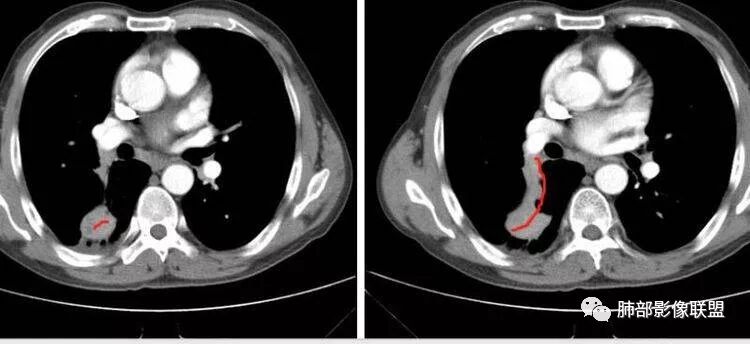

M-Imaging :病人胸痛20天,病灶三角形宽基底与胸膜贴近,肺门侧支气管通畅,造影显示肺动脉狭窄,考虑肺动脉栓塞,肺梗死?HeKate·Awizard·Sinitici:老师,请教一下,这是联盟讲座里说到的支气管爬行征吗?M-Imaging :我觉得像肺梗死,支气管通畅的采莲:中老年男性,右肺下叶背段片状影,边缘收缩平直,会不是异物可能么呢?中老年男性,咳嗽咳痰发热,急性起病,右肺下叶背段片状影,边缘收缩平直,周围有点片影,考虑异物合并感染,鳞癌待排。南边:多种意见:肺梗死、结核、异物、鳞癌肺动脉还好吧

南边:紧贴着斜裂过来的一个病灶,它的特点是:外围大,内带小。它整个下叶背段体积与对侧相比稍微缩小一点,但是缩小地不是很厉害。外支朝前下走了,仔细看血管,肺动脉走行自然,直达远端。远端实变区是肉芽肿成分,稍微有一点低密度,没有明显坏死,稍微有一点点坏死。而且附近有很多卫星灶,附近很多斑片影,有一些明显有气道壁增厚,细支气管炎的特点,还有就是下叶其他段很多斑片状影。换个角度,第一如果是肺癌,刚才看到PET-CT提示肺癌伴阻塞性肺炎,这个是不符合的。第二如果是肺癌阻塞性肺炎,近端血管肺动脉走行不会那么自然集聚的,这个是不符合的。理由是:如果这个病灶是肺癌,那么明显属于中央型肺癌,中央型肺癌的特点是近端大,远端小,近端是一个肿块,远端阻塞,远端阻塞是阻塞性炎症或者不张,它应该体积缩小,斑片状实变,不会这么密实。刚才有老师提到支气管,这个片有缺陷的地方,给的图像好像那层,如果把其他图像拿开再重叠一下。

如果是单纯看这幅图像,会觉得背段外侧支气管分支堵塞的,但是看下面这层图

南边:你就发现外侧支气管朝下走的分支非常自然,通畅的。

南边:这个肺门区,11区和7区都有一些淋巴结,淋巴结的形态不是类圆形,而是梭形的。这个病灶给的图比较少,个人倾向,第一强化非常均匀,肉芽肿性病变;第二,里面血管走行非常自然,远端大近端小,倾向炎性,特别是下面还有斑片状影,非阻塞远端,支气管远端病灶下叶背段,其他段也有,所以我倾向炎性;另外,它里面整个走行符合支气管树爬行征,我倾向结核可能,首先我定在炎性,其次有没有结核的可能。